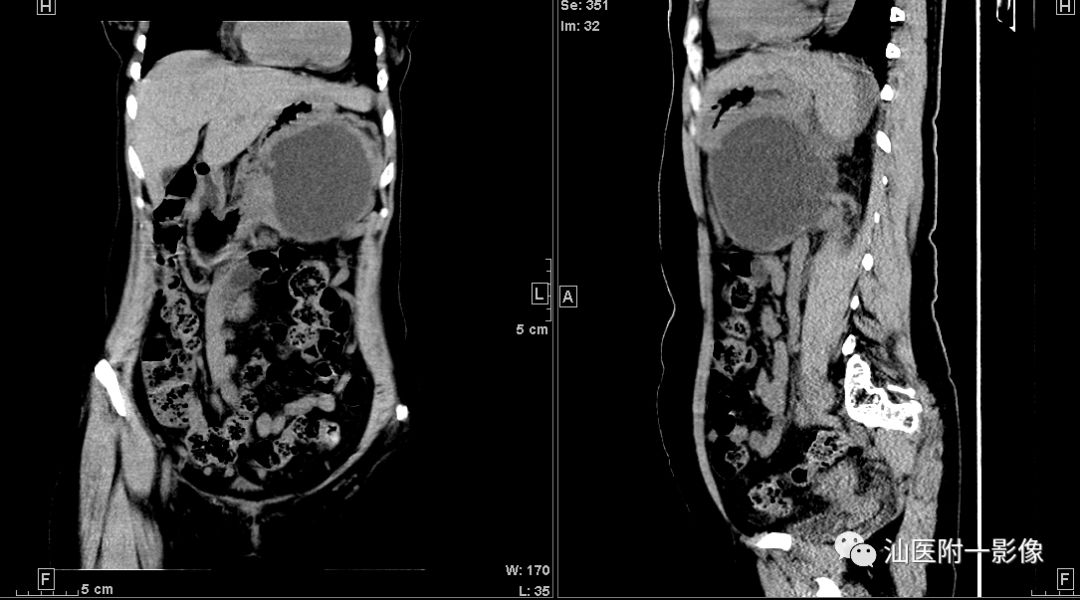

病例2

病例二 胰腺假性囊肿